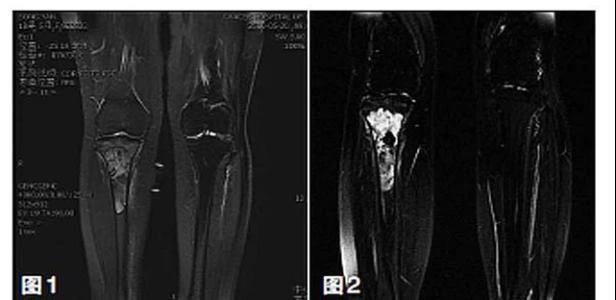

新輔助化療的目的是盡早殺滅遠處微小轉(zhuǎn)移灶,縮小腫瘤及周圍炎性水腫反應區(qū),以利于后續(xù)的保肢手術;觀察腫瘤對化療的敏感性,為進一步指定個體化的術后化療方案奠定基礎。骨肉瘤新輔助化療下的保肢治療如下圖所示: